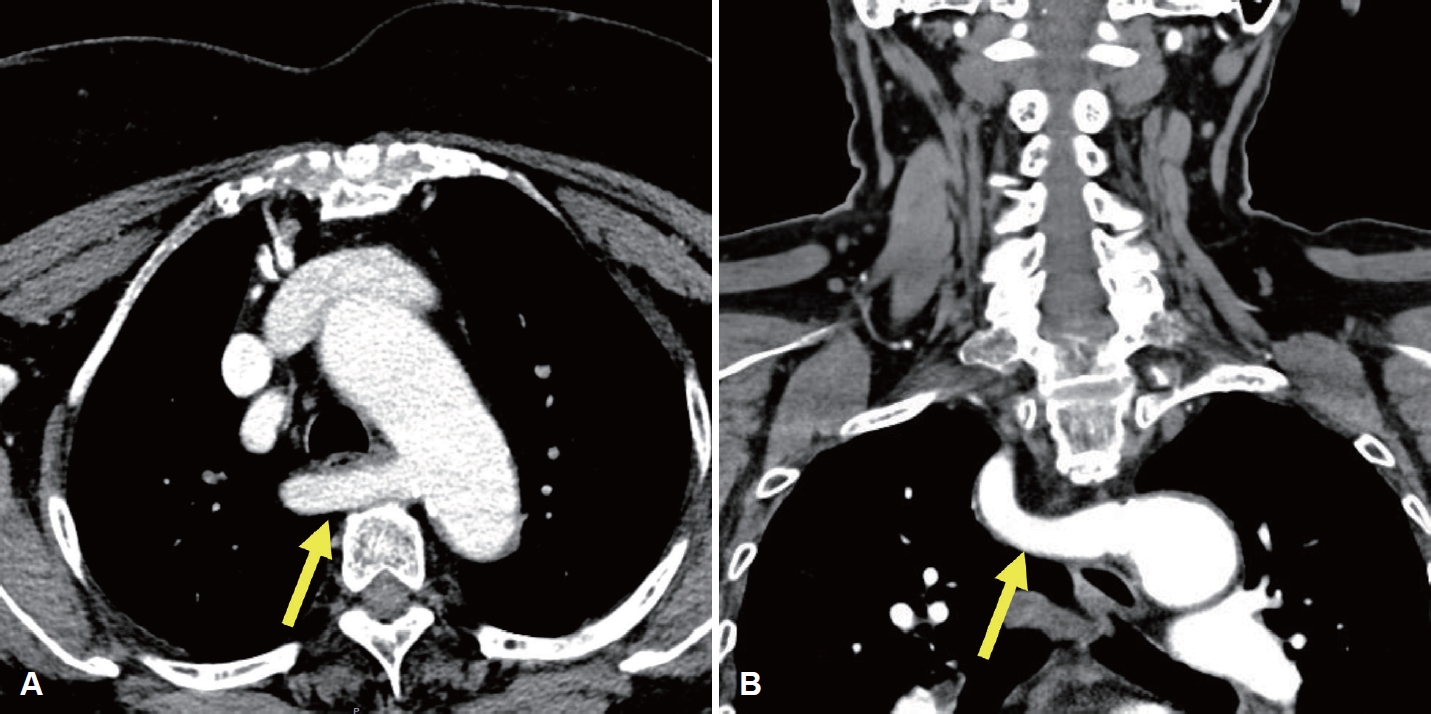

증 례78세 여성이 한 달 전부터 발견된 전방 경부 종괴를 주소로 내원하였다. 신체검사 및 촉진 결과 갑상선 종괴가 의심되었고, 수일 후 시행한 초음파 검사에서 좌측 협부에 44 mm 크기의 갑상선 결절이 확인되어 중심바늘생검(core needle biopsy)을 시행하였으며, 갑상선 유두암(papillary thyroid cancer)이 진단되었고 초음파와 조영증강 갑상선 CT (thyroid CT)를 시행하였으며 수술 전 임상병기는 cT3bN0으로 판정되었다. 경부 초음파 검사는 고해상도 초음파 기기(EPIQ7, Philips Healthcare)와 5-12 MHz 선형탐촉자를 사용하여 갑상선 및 두경부 초음파에 숙련된 영상의학과 전문의에 의해서 수행되었다. 조영증강 갑상선 CT는 갑상선암 진단에 최적화된 대한갑상선영상의학회에서 제시한 표준검사기법으로 수행되었으며[1], 조영제 주입 후 35초 시점에 영상이 획득되었고, 2 mm 절편 두께로 횡단면, 관상면, 시상면 영상이 재구성되었다. 갑상선 전절제술 및 중앙 경부절제술을 계획하였고 thyroid CT에서 우측 이상 쇄골하동맥이 확인(Fig. 1)되어 비반회후두신경 가능성을 고려하여 비반회후두신경 평가를 위해 수술 전 경부 초음파를 추가로 시행하였다. 비반회후두신경의 초음파 평가는 설골 부위에서부터 미주신경을 초음파로 확인한 후에 미주신경을 하방으로 연속적으로 추적하여 미주신경에서 내측으로 분지되는 신경 유무를 평가하였다. 본 증례에서는 초음파 검사에서 갑상연골 높이의 미주신경으로부터 직접 분지되어 총경동맥 후방 쪽으로 주행하는 저에코의 신경 가지를 확인하였다(Fig. 2). 이후 예정된 수술을 시행하였으며, 피부 절개 후 갑상선 검체를 박리하는 과정에서, 한국 표준화된 신경모니터링 방법2)을 사용하여 수술 중 신경모니터링을 적용하였고, 모니터는 잘 작동하였다. 수술 시 type II 비반회후두신경을 확인하였으며(Fig. 3), 수술 중 신호손실(loss of signal) 등의 문제는 없었으며, 수술 직후 및 외래 추시 시 내시경 검사에서 성대마비는 관찰되지 않았으며(Fig. 4), 입원 중 특이 합병증이 관찰되지 않았다. 병리 결과는 유두암, 고전형(classical type), 단일 결절(3.9×3.0×3.0 cm), 갑상선 외 침범(macroscopic extrathyroidal extension) 및 좌측 6번 경부 구획에서 한 개 림프절에서 미세 림프절 전이가 확인되었다. 림프혈관 침윤, 신경 침윤, 외측 절제면 침범은 없었다. 환자는 내분비내과에서 정기적인 추적 검사를 진행하며, 방사선 요오드 치료(radioactive iodine)를 권고하였으나 환자의 의사에 따라 시행되지 않았다. 내분비내과에서는 권장했지만, 환자는 이를 거부하였다. 추적 검사에서는 T3, T4, 갑상선자극호르몬, 갑상선글로불린 등을 포함한 갑상선기능 검사 및 화학검사에서 정상 범위 수치를 보였다.

Fig. 1.Preoperative enhanced thyroid CT images of an ARSA. A: Axial enhanced CT shows the ARSA (arrow) arising from the aortic arch and coursing posterior to the esophagus. B: Coronal enhanced CT shows the retroesophageal ARSA (arrow). ARSA, aberrant right subclavian artery. Fig. 2.Serial ultrasonographic tracking images of the NRLN obtained using a 5–12 MHz linear-array transducer. A-F: A series of transverse ultrasound images arranged in craniocaudal order shows the suspected right NRLN (yellow arrowheads). A and B: The right vagus nerve (white arrowheads) is visualized between the IJV and CCA at the level of thyroid cartilage. C and D: A nerve branch is seen arising directly from the right vagus nerve. E and F: The nerve branch courses horizontally and medially toward the CCA. G and H: The descending vagus nerve (white arrowheads), separated from the NRLN, is seen at the level of the cricoid cartilage and thyroid gland. This direct, non-recurrent path from the right vagus nerve at the level of the larynx is highly suggestive of an NRLN. NRLN, non-recurrent laryngeal nerve; IJV, internal jugular vein; CCA, common carotid artery. Fig. 3.Intraoperative identification of the NRLN. The right NRLN is indicated by a yellow arrowhead during thyroidectomy. The green arrowhead indicates the electrode positioned on the perichondrium of thyroid cartilage. NRLN, non-recurrent laryngeal nerve. Fig. 4.Postoperative laryngoscopy showing vocal cord function. A: Laryngoscopy on POD 11 complete abduction during inspiration. B: Laryngoscopy on POD 11 also shows complete adduction during phonation. C: Laryngoscopy on POD 4 years reveals improved vocal cord movement. Both vocal cords are fully abducted during inspiration. D: Laryngoscopy on POD 4 years shows full adduction of both vocal cords during phonation. POD, postoperative day. REFERENCES1. Ha EJ, Chung SR, Na DG, Ahn HS, Chung J, Lee JY, et al. 2021 Korean thyroid imaging reporting and data system and imaging-based management of thyroid nodules: Korean Society of Thyroid Radiology consensus statement and recommendations. Korean J Radiol 2021;22(12):2094-123.